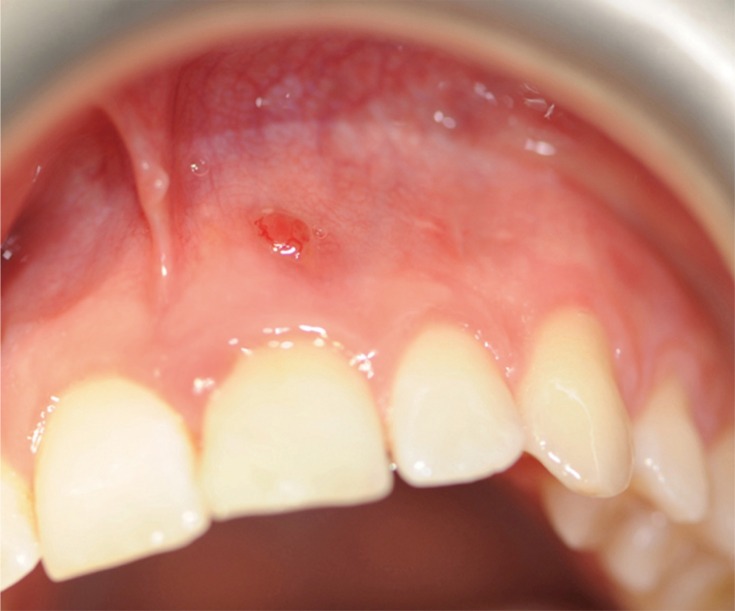

A clinical examination showed a moderate swelling on the vestibular side in the region of tooth #21, as well as the presence of a sinus tract in the same area, approximately 4 mm from the gingival margin (Figure 1). A narrow periodontal defect 7 mm in depth was present on the buccal side, as evaluated using a periodontal probe. A radiographic examination performed before surgery using both periapical radiographs and CBCT (J. Morita MFG Corp., Kyoto, Japan) revealed a root-end resection, a periapical radiolucency, and a widening of the periodontal ligament space at the mesial aspect of the root, although no hair-like fracture line radiolucency was noted in the tooth, except in the CBCT horizontal projection that showed an incomplete VRF 3 mm from the apex (Figure 2).